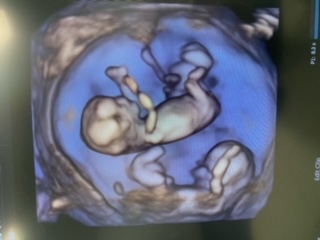

Hi everyone, just wondering if it's possible to see a nub on this image which was taken at 11w6d (although babies were measuring 13 weeks) unfortunately this is the only image I have as I've had to go through the hospital due to some health concerns so I'm not sure if anything is visible at all. I was swaying girl last year then decided I was done with babies only to get pregnant (first surprise) and found out it was identical twins (second very big surprise!). We won't be finding out gender til birth although I really want to know, I think they're boys and this is a boyish nub but I'm terrible at this so just hoping someone can have a look! Thank you!

Attachment 43314